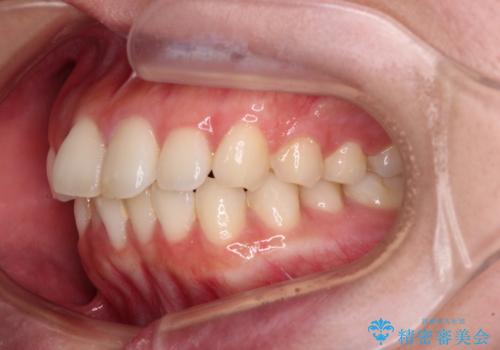

- 全体的なデコボコと口元の突出感を改善したいとのことで来院された患者様です。

このままデコボコを整えるとさらに突出感が増すため、上下左右の第一小臼歯を抜歯し、ワイヤー装置にて矯正しました。

結婚式で途中装置を外した時期がありましたが、2年で治療を終えることができました。